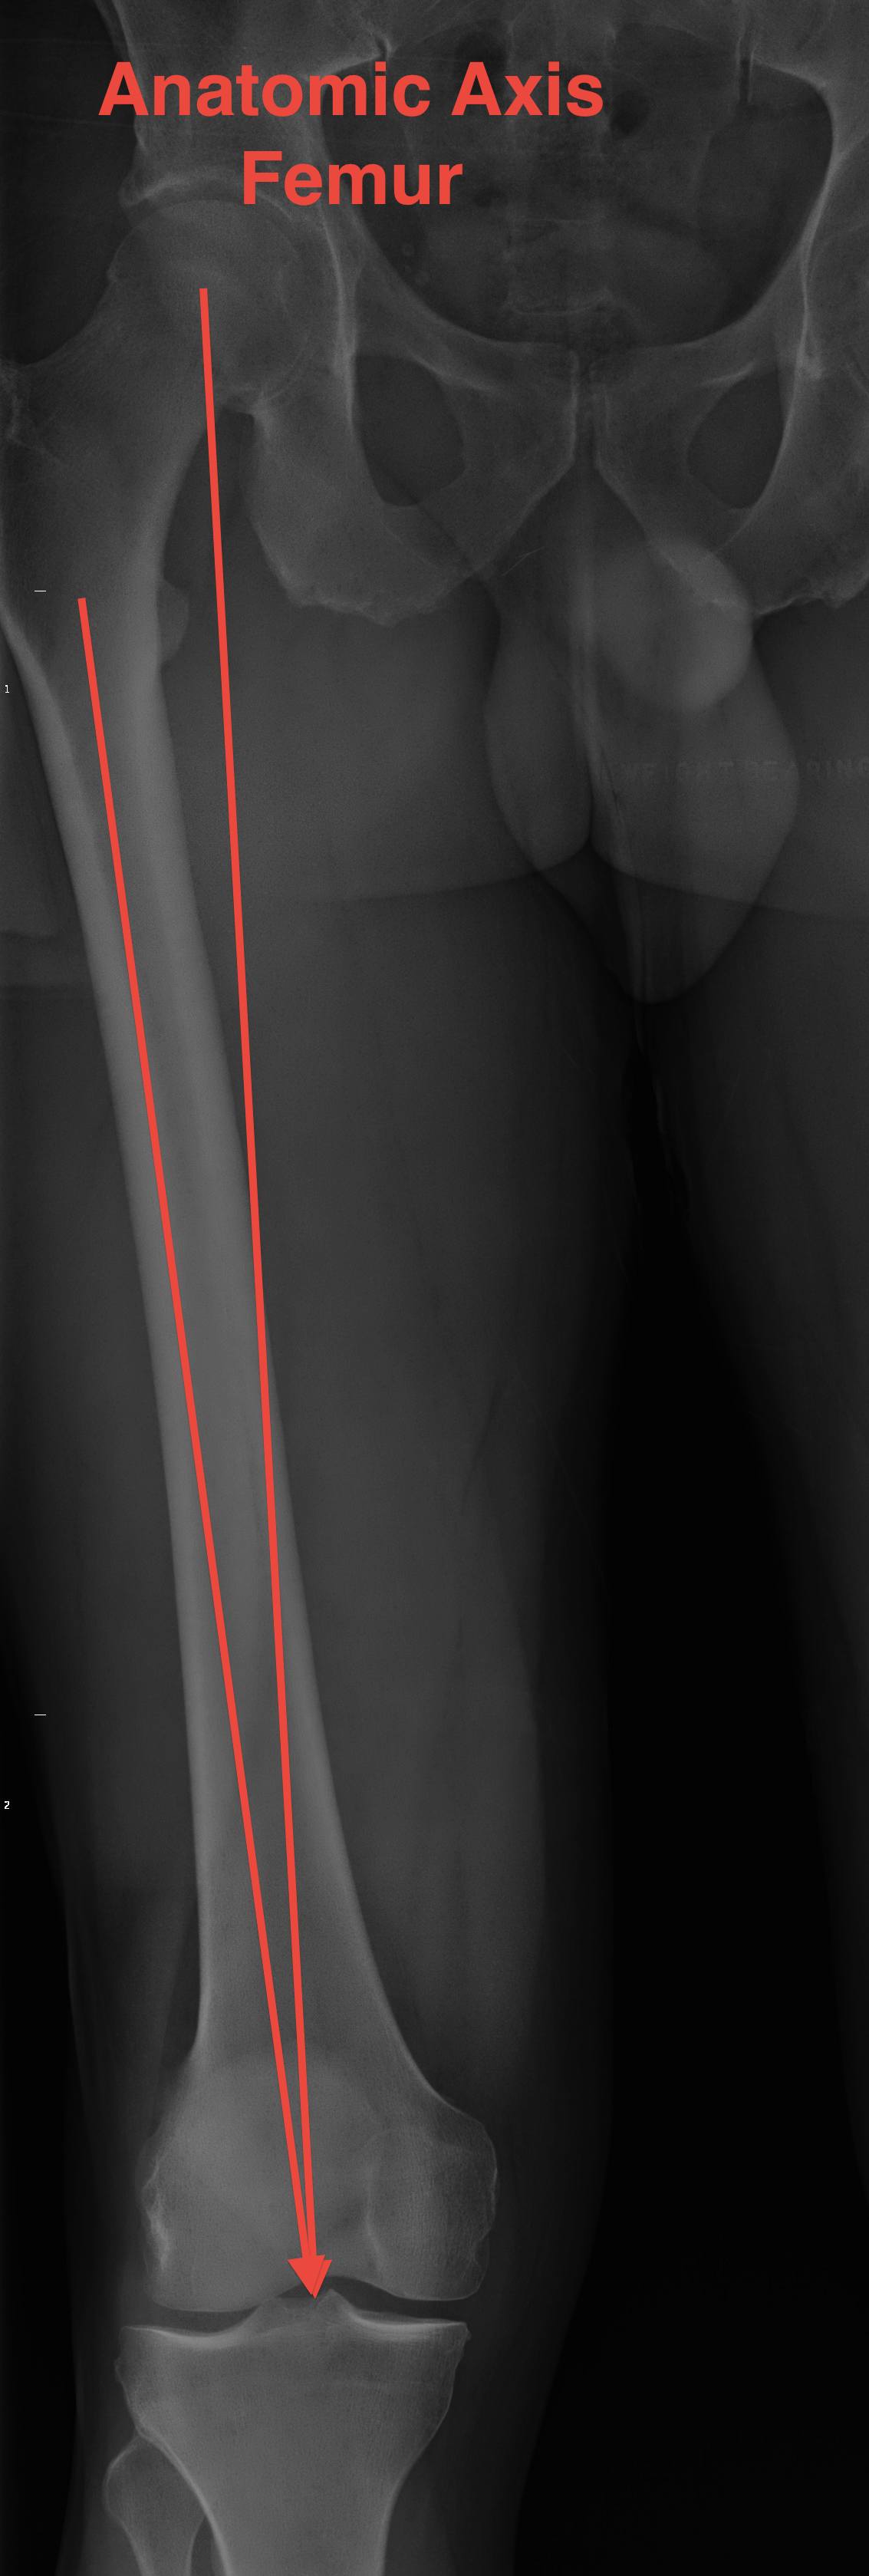

Anatomical Axis Femur (AAF)

- centre of femoral medullary canal to midpoint whiteside's axis

- usually exits at intercondylar notch

- entry point for IM rod of femoral jigo

Valgus cut angle

- angle between femoral and mechanical axis

- LL standing AP

- usually between 5 and 7o

- if cut the distal femur at the valgus cut angle, will place the femoral prosthesis mechanically neutral

Short patients - > 7o

Very tall patients - < 5o